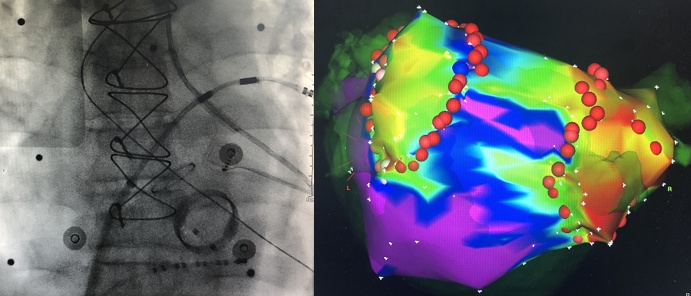

①房颤消融杂交治疗:瓣膜病房颤、外科术后房扑等内外科杂交手术策略,提高复杂房性心律失常治疗成功率。房颤冷冻球囊消融术、机器人磁导航指导房颤消融术、传统手工导管房颤量化消融术是瑞金医院房颤消融术的优势技术,是国内能同时开展这三项技术仅有的几家中心之一。瑞金医院是国内最早开展房颤冷冻球囊消融术的中心之一,吴立群主任牵头制定国内首部房颤冷冻球囊消融专家共识,积极推广该项技术的应用。2019年,瑞金医院成为亚洲地区首家磁导航指导消融术突破1000例的中心,近3年磁导航手术量亚洲地区第1,2019年全球第2。

心脏内外科联合治疗:磁导航指导二尖瓣+主动脉瓣置换术后房扑/房颤消融

②器质性室速消融:心肌病室速(室壁瘤、心外膜起源)的内外科标测和消融策略,提高消融成功率。